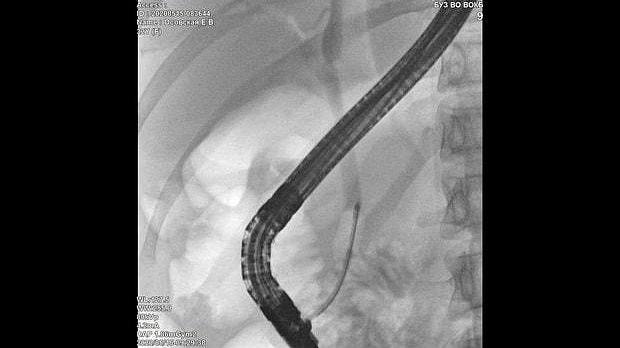

Здравствуйте. Пациентка, 32 года. Поступила на хирургическое отделение с диагнозом ЖКБ: холедохолитиаз. По данным МРТ: ЖКБ, множественные мелкие конкременты холедоха. При дуоденоскопии выявлено наличие вклиненного конкремента большого дуоденального сосочка. Выполнена прекатсфинктеротомия, получено 3 конкремента, диаметром около 0.4-0.5 см. Далее канюляция холедоха проволочным папиллотомом, выявлены многочисленные конкременты холедоха. Выполнена литоэкстракция ревизионным баллоном (на последнем фото окклюзионная холангиография - в просвете холедоха не конкременты, а пузырьки воздуха)).